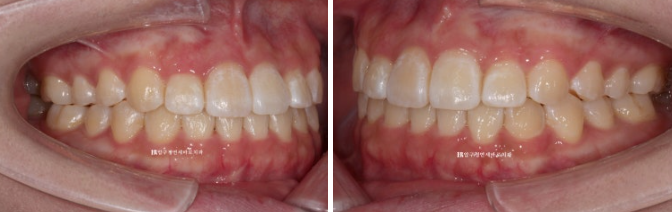

23.04~24.01

앞니 각도 전 후 변화 입니다.

웃을 때 치아가 일자로 딱 떨어지는 모양새가 보기 좋습니다.